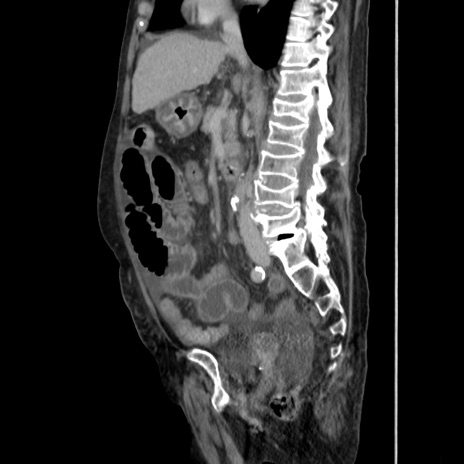

症例31(矢状断像)

【症例】80歳代 女性

【主訴】腹部膨満感

【現病歴】他院にて肝硬変にてフォロー中。1週間前から便秘、腹部膨満感、臍部腫瘤あり受診となる。

【既往歴】肝硬変

【身体所見】腹部膨隆あり、皮膚変化なし、疼痛なし。

【データ】WBC 4600、CRP 0.25